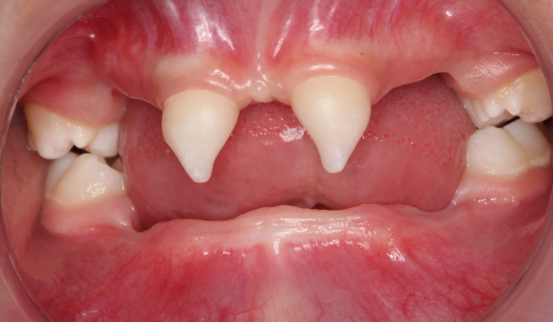

近年来,3044永利集团附属口腔医院(后文简称贵医口腔)在临床诊疗方面每年均有多个技术创新或突破。期间,副经理、口腔修复种植科主任医师王永曾带领团队完成多名外胚层发育不全患儿的可摘局部义齿及全口义齿修复,222日,更是为一位4岁患儿完成了罕见外胚层发育不全可摘局部义齿修复该患儿为目前口腔医院完成修复治疗年龄最小的患者

患者4岁,乳牙未正常萌出,上颌仅4下颌仅2颗乳牙,不能正常咀嚼,于2022年底在外地就诊多次无法修复,专程到口腔医院就诊。在后疫情时期,患者经王永门诊诊治后商讨出诊疗方案医院细心安排,于222由王永带领谭雯珈、姜炜鹏等医师,使用修复、正畸、修复工艺等多项技术,顺利完成了大面积乳牙缺失修复患儿现场进食效果良好,家长及患儿十分满意。

口腔修复种植科作为贵州省临床重点学科及专科,在罕见病、疑难病的诊断和治疗上有特色鲜明的治疗项目MDT协作诊疗模式更是十分成熟,此次诊疗在医护技团队通力协作下,为减少患儿就诊次数及周期,减轻家长异地就诊负担,压缩诊疗周期,当日便根据诊疗方案完成个性化复杂可摘局部义齿椅旁制作患儿佩戴上义齿露出笑容患儿家属对修复种植科团队的真诚谢意,充分给予了医务人员成就感和满足感,贵医口腔将会持续提升技术软实力,帮助更多患者找回自信微笑。

因其口腔表征为先天缺牙甚至无牙颌,且缺牙患儿口内余留牙往往表现为锥形牙、釉质发育不良、牙槽嵴发育不良等,可严重影响患儿的咀嚼功能及面部软硬组织生长发育。